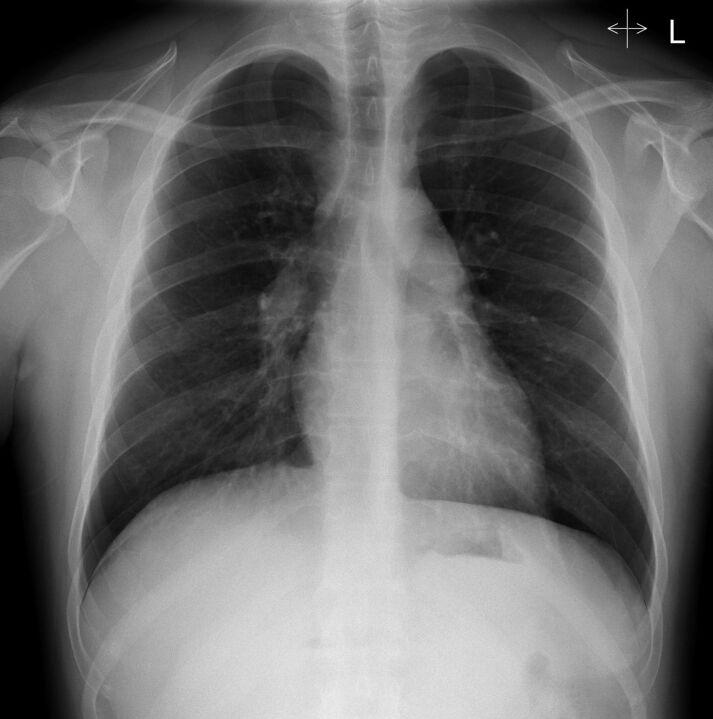

一名25岁男性出现进行性呼吸困难和弥漫性纵隔淋巴结肿大的有趣病例。

An interesting case of progressive dyspnoea and diffuse mediastinal adenopathy in a 25-year-old man.